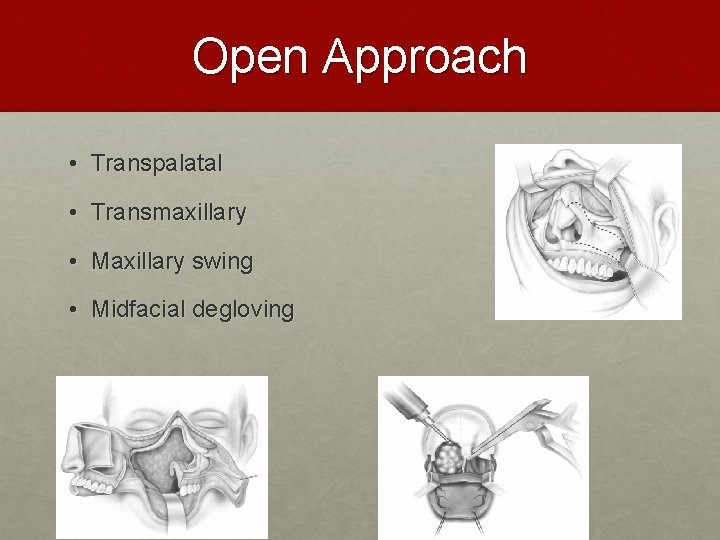

Open Approach • Transpalatal • Transmaxillary • Maxillary swing • Midfacial degloving